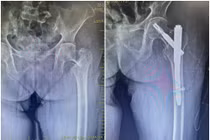

Các bác sĩ Bệnh viện Đa khoa Khu vực Quảng Yên vừa phẫu thuật thành công ca thay khớp háng bán phần chuôi dài cho cụ bà 91 tuổi bị gãy liên mấu chuyển xương đùi trái – một trường hợp hiếm gặp, có nhiều yếu tố nguy cơ phức tạp do tuổi cao, sức yếu và mắc nhiều bệnh nền.

Biến chứng nguy hiểm do gãy liên mấu chuyển xương đùi

Phẫu thuật kết hợp xương ít xâm lấn điều trị gãy liên mấu chuyển xương đùi giúp người bệnh hồi phục nhanh, tránh biến chứng nguy hiểm.

Bệnh viện Đa khoa tỉnh Quảng Ninh đã hỗ trợ Bệnh viện Đa khoa Hạ Long thực hiện phẫu thuật kết hợp xương ít xâm lấn điều trị gãy liên mấu chuyển xương đùi cho hai bệnh nhân cao tuổi.

Ca mổ không chỉ giúp người bệnh hồi phục nhanh nhờ phương pháp hiện đại mà còn khẳng định vai trò tuyến chuyên sâu trong hội chẩn, hỗ trợ chuyên môn, giúp người dân vùng xa được tiếp cận kỹ thuật điều trị tiên tiến ngay tại địa phương.